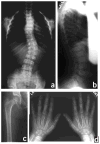

The brachyolmias constitute a clinically and genetically heterogeneous group of skeletal dysplasias characterized by a short trunk, scoliosis and mild short stature. Here, we identify a locus for an autosomal dominant form of brachyolmia on chromosome 12q24.1-12q24.2. Among the genes in the genetic interval, we selected TRPV4, which encodes a calcium permeable cation channel of the transient receptor potential (TRP) vanilloid family, as a candidate gene because of its cartilage-selective gene expression pattern. In two families with the phenotype, we identified point mutations in TRPV4 that encoded R616Q and V620I substitutions, respectively. Patch clamp studies of transfected HEK cells showed that both mutations resulted in a dramatic gain of function characterized by increased constitutive activity and elevated channel activation by either mechano-stimulation or agonist stimulation by arachidonic acid or the TRPV4-specific agonist 4alpha-phorbol 12,13-didecanoate (4alphaPDD). This study thus defines a previously unknown mechanism, activation of a calcium-permeable TRP ion channel, in skeletal dysplasia pathogenesis.